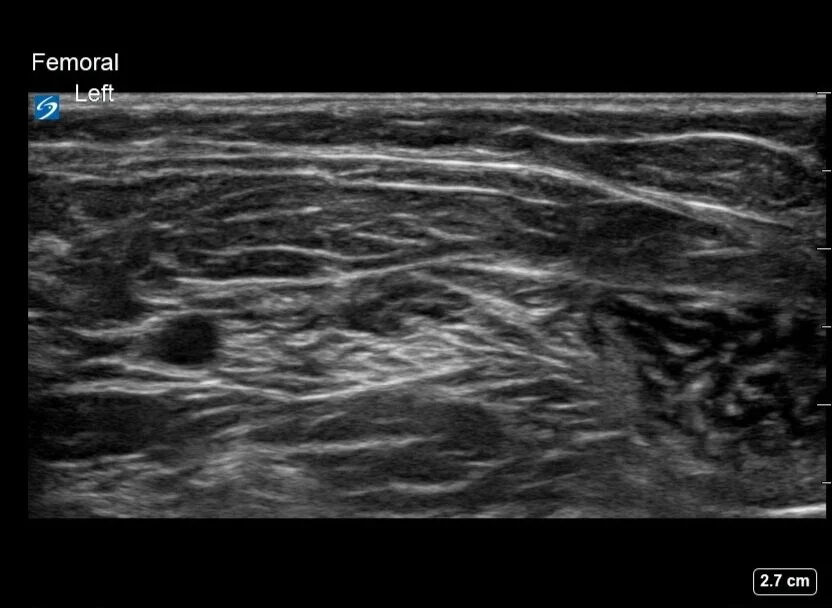

The femoral nerve may be identified as a hyperechoic structure just lateral to the femoral artery. In the ideal case, it can be seen immediately lateral to the femoral artery, as a bright “cluster of grapes”. Realistically, especially in our smallest of patients, its shape may be triangular, oblong, or very flat, and may lie more lateral than is classically seen in ideal adult patient examples.

Another tip is to keep the probe perpendicular to the long axis of the leg, find the femoral artery bifurcation and then trace the artery back proximally 1-2cm. Now identify the iliopsoas muscle. The femoral nerve lies on top of the iliopsoas muscle, and the sartorius muscle should overlay the lateral half of the iliopsoas muscle (thanks to Dr. Peter Merjavy and Dr. Robbie Erskine for the tips!)

Ultrasound Images